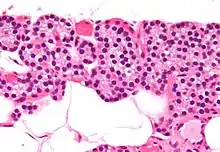

Histologicamente, as paratiroides apresentam dois tipos de células: as principais e as oxifílicas. As células principais são menores e abundantes, e são elas que secretam a PTH. As células oxífilicas são maiores, mais eosinófilas (devido à sua abundância de mitocôndrias) e têm função desconhecida. Cada glândula é envolvida por uma cápsula própria, da qual se projetam feixes de tecido conjuntivo que dividem o interior da glândula em lóbulos.

Os dois tipos de células, principais e oxífilicas, são sustentadas por uma matriz de tecido conjuntivo reticular e adiposo.

Células oxifilas em coloração por hematoxilina e eosina,apresentam o seu núcleo intensamente corado pela hematoxilina,enquanto que seu citoplasma homogeneo e corado pela eosina,estas células não secretam PTH,a função celular é desconhecida

As células principais,apresentam núcleo densamente corado e o citoplasma também intensamente coradas, estas células são responsáveis pela secreção do hormônio Paratormônio(PTH).As células principais,normalmente se apresentam como uma coloração mais escuras,o que denota uma atividade nuclear e enzimática ativas,enquanto que as células claras, são denominadas assim por serem células principais em repouso,em que não é observado a produção de PTH,mas no seu citoplasma tem acumulo de lipídeos e glicogênio.